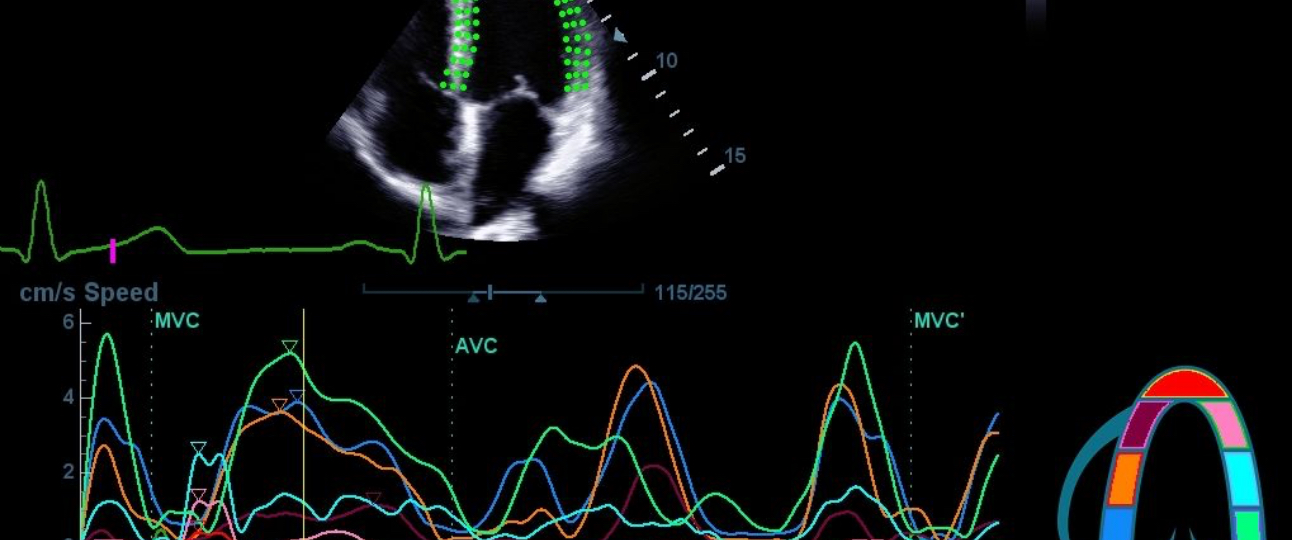

In cardiac and vascular applications, this ultrasound system shows a lively performance; and with the support of advanced features such as Auto EF and Smart Track, it always presents dynamic imaging results, not only for basic images of heart and vessels, but also in multiple modes including Color, PW, TDI and TTQA.

TDI QA (Tissue Doppler Imaging Quantification Analysis)

TTQA (Tissue Tracking with Quantitative Analysis)